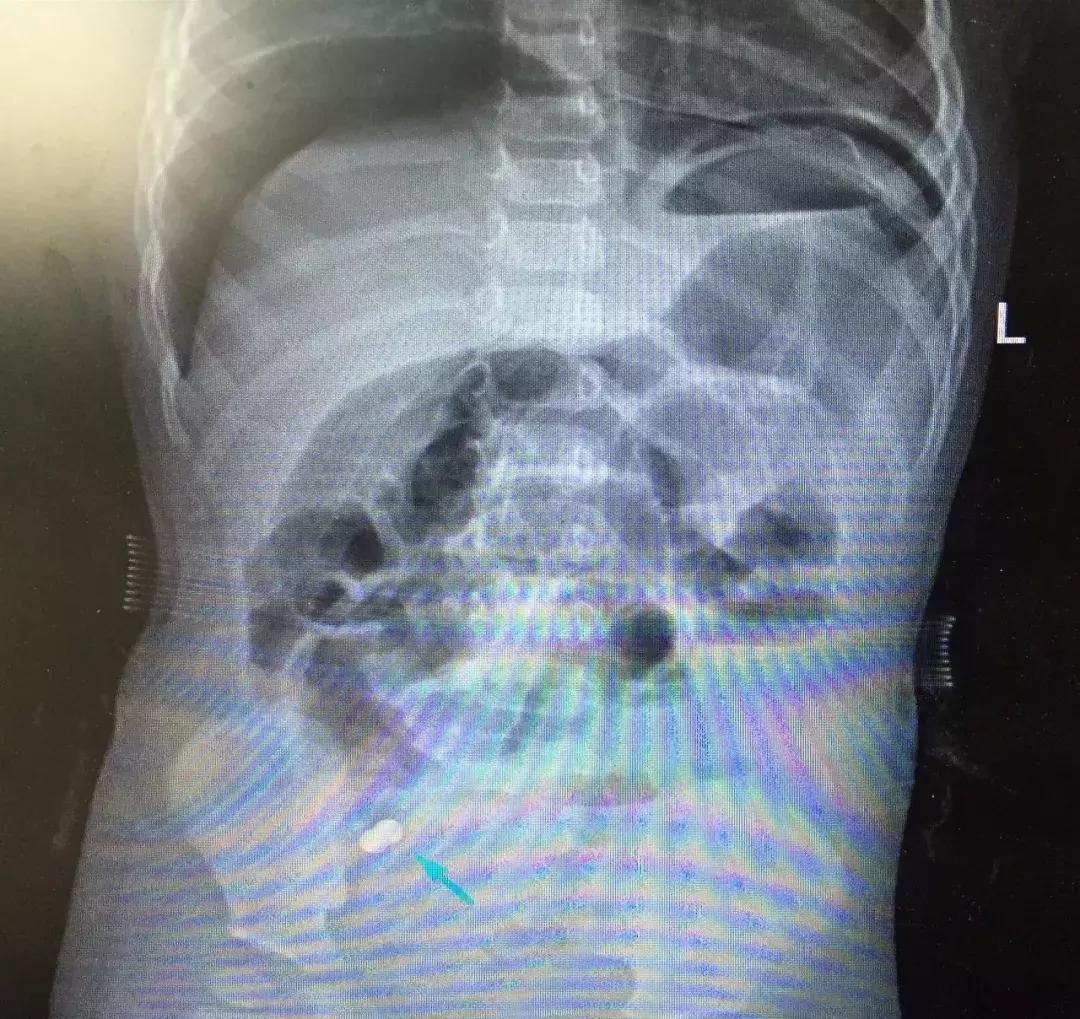

拍过腹部X光片后,结果竟然提示琪琪消化道穿孔、下腹部异物!情况紧急,胃肠外科的医生经过会诊并向主任田永静汇报病情后为琪琪安排了急诊手术。手术由胃肠外科主任孙海滨主刀、主治医师恩日乐图协助,从琪琪腹腔取出两颗直径约3mm的磁力球,并对穿孔的肠道进行修补。

“经术中检查确认2颗磁力球已经进入了肠道,并出现了肠穿孔及出血等症状,当时琪琪的已经出现了感染性休克,如果不及时进行治疗可能会危及生命”胃肠外科医生恩日乐图介绍。